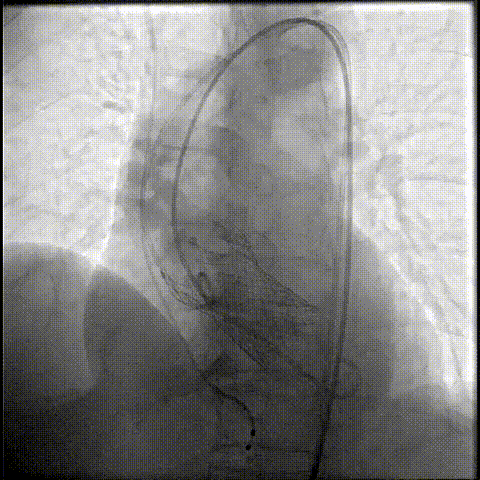

释放瓣膜

80%工作位评估

23球囊后扩

最终造影形态位置良好,轻微瓣周漏

术后压差降为0mmHg